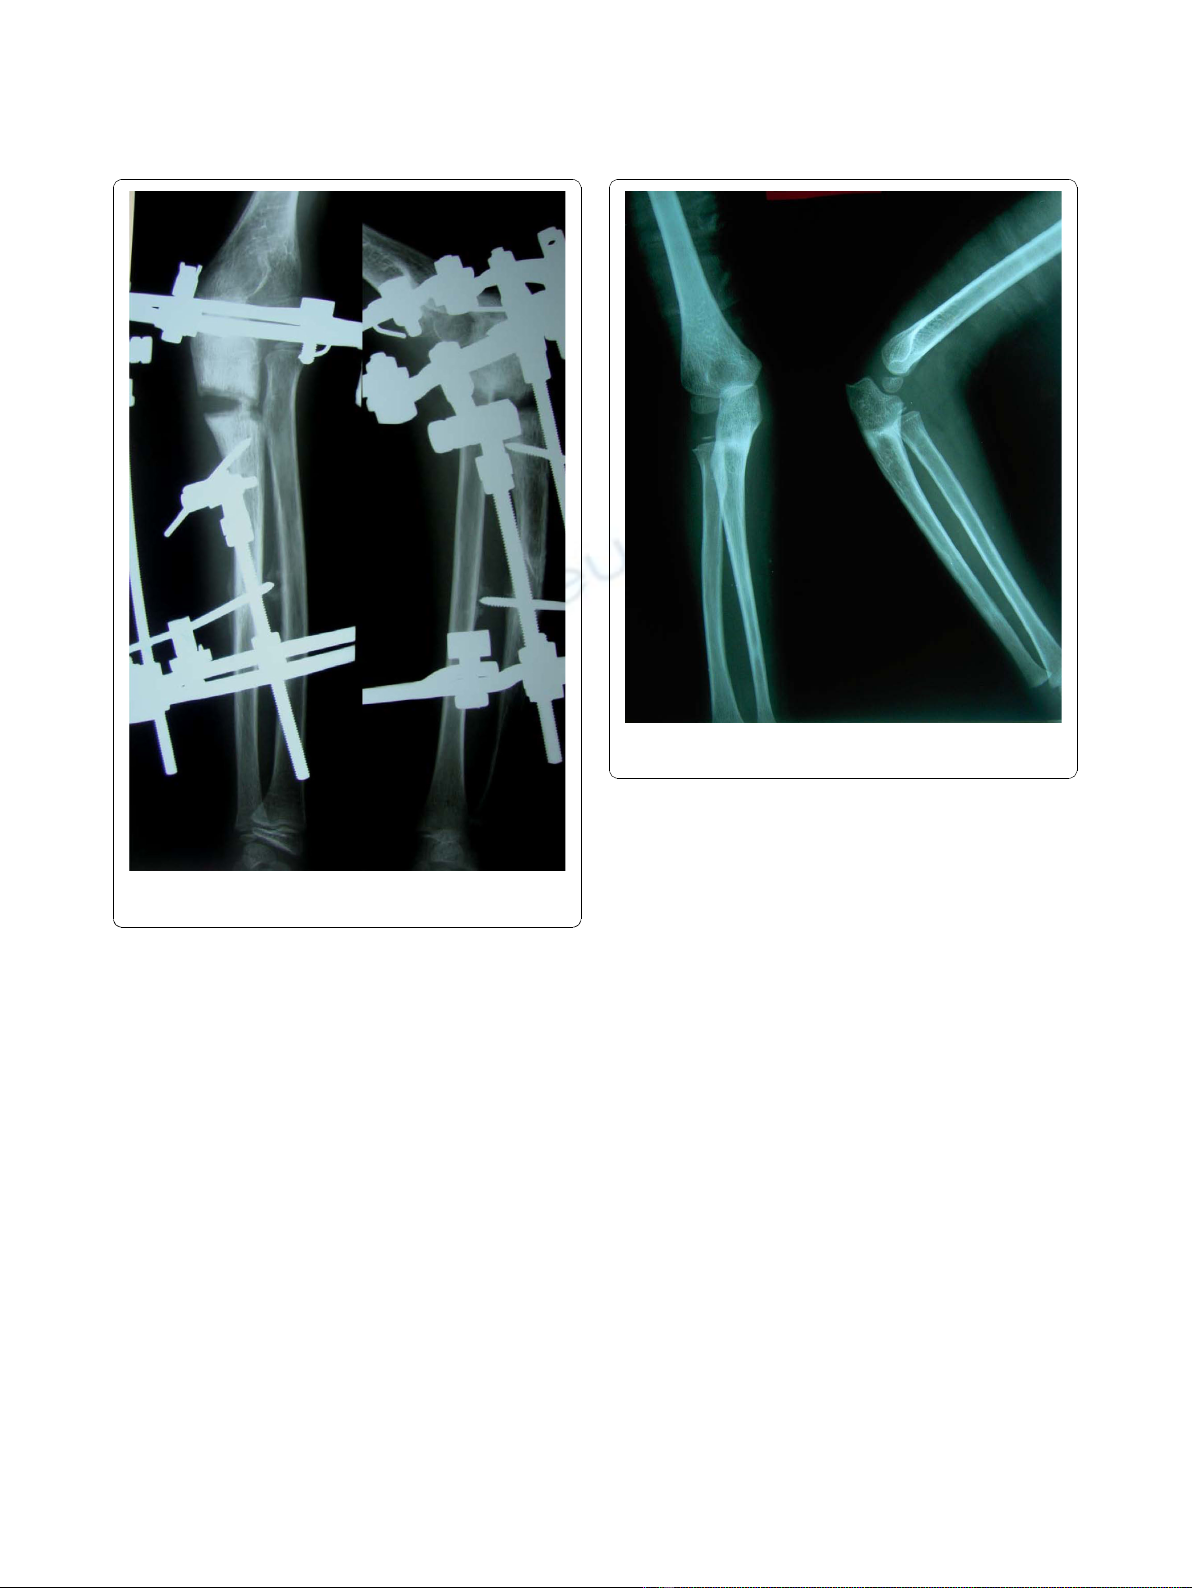

In both cases, an anterolateral dislocation of the radial

head was confirmed by radiography. An underlying

ulnar injury in both our cases was suspected because of

the loss of proximal convexity of ulna (Figure 1).We

Radiographs in both anterio-posterior and lateral view

were studied to assess the dislocation of the radial head.

Because the dislocation in both of our patients was an

anterolateral one (Figures 1, 2), an osteotomy in the

proximal ulna and differential lengthening in two planes

was planned to create a medial (Figure 3) and posterior

(Figure 4) hyperangulation, to place the radial head in

the appropriate radiocapitellar orientation. We hoped to

avoid open reduction of the dislocation and reconstruc-

tion of the annular ligament.

Figure 1 Preoperative radiograph of patient 1 showing

Monteggia fracture dislocation (Patient 1).

Figure 2 Preoperative radiograph showing radial head

dislocation (Patient 2).